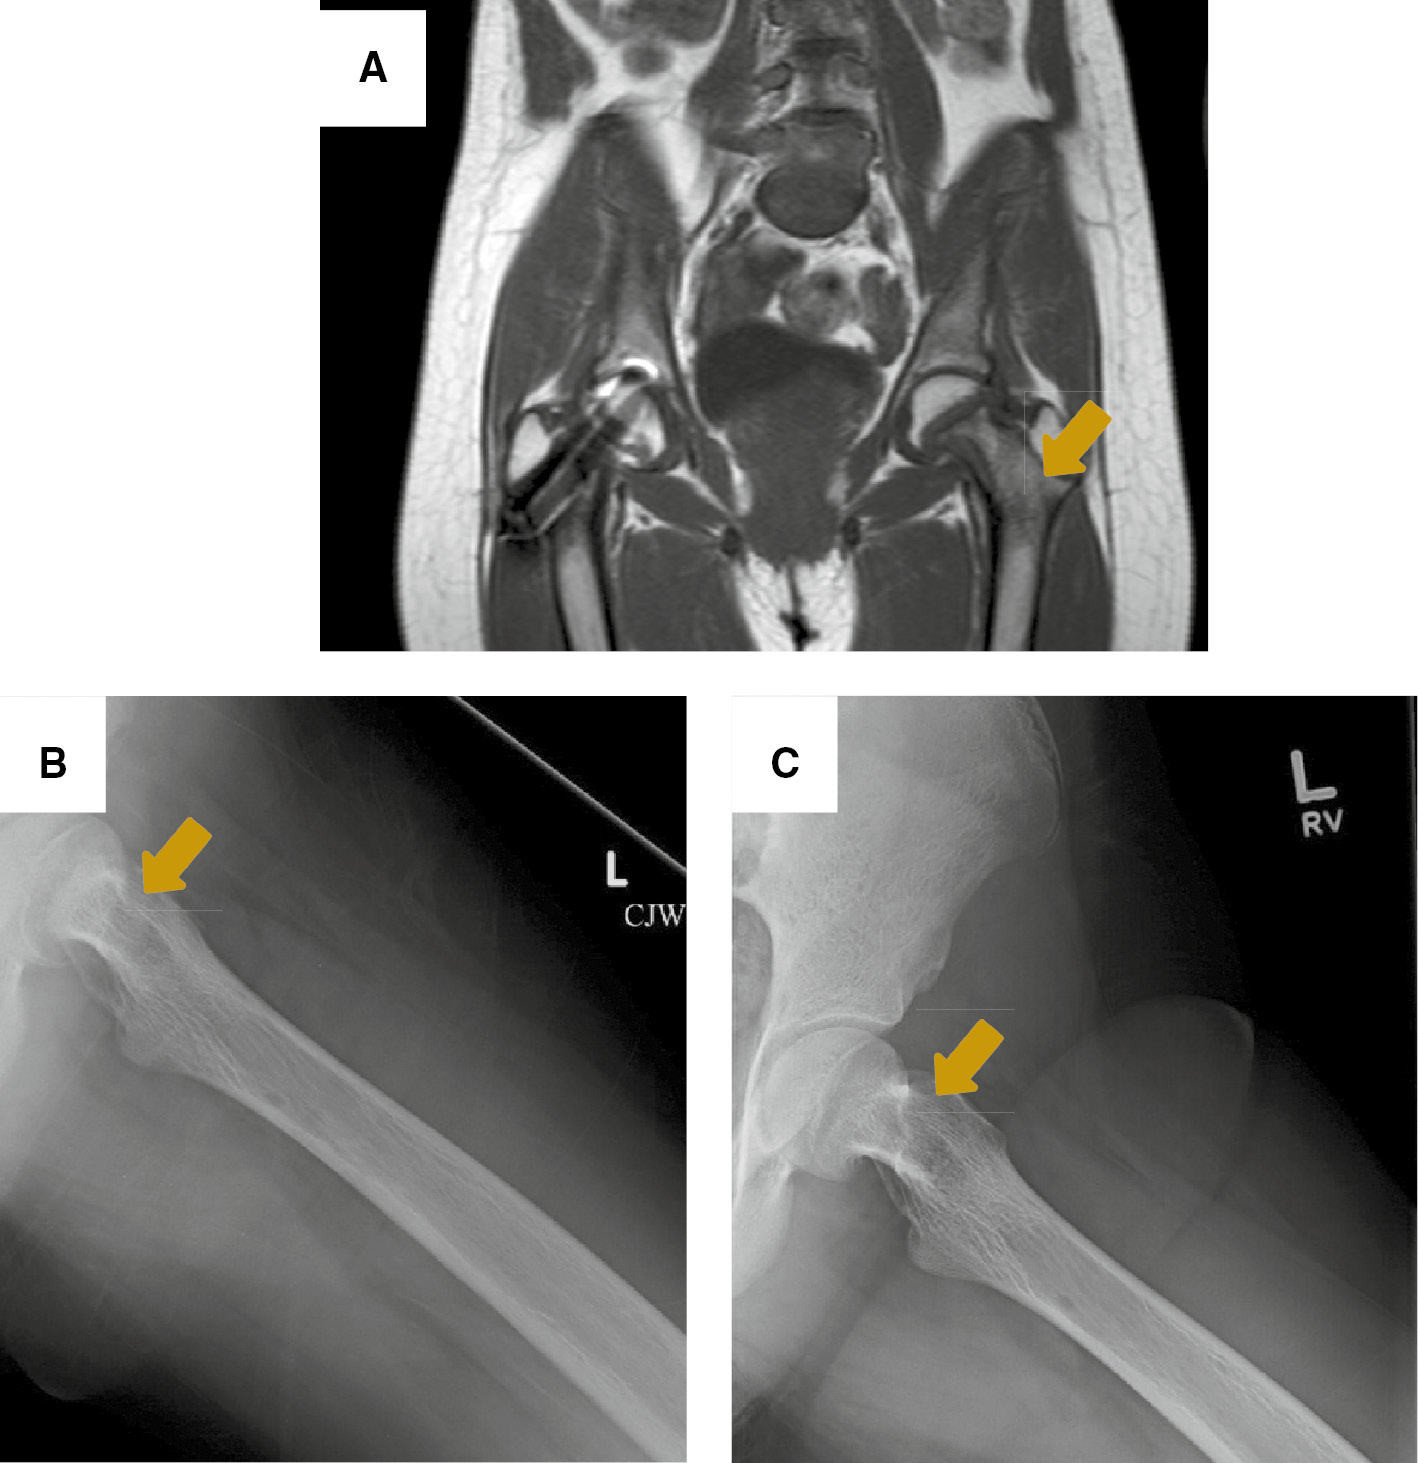

The patient underwent left neck exploration and parathyroidectomy with recurrent laryngeal nerve monitoring. At the time of surgery, a firm, 3.5×3×1.3 cm left inferior parathyroid mass was encountered, and found to be adherent to surrounding tissues, including the anterior tracheal wall fascia, the left inferior thyroid, and the left thymic tongue; thus, a wide local excision was performed. There was no cervical adenopathy identified in the tracheoesophageal groove, but the left recurrent laryngeal nerve was significantly displaced laterally by the tumor. En-bloc resection of the tumor along with a left inferior thyroid lobectomy was performed. The performed neck dissection included an ipsilateral selective neck dissection of levels III and IV from the left common carotid artery laterally to the anterior tracheal wall fascia medially and a complete level VI lymph node dissection down to the brachiocephalic artery including the thymic tongue. The neck exploration was limited to the ipsilateral and central neck compartments as the tumor did not cross midline, intraoperative frozen sections on all surgical margins were negative for tumor, and there was no clinical lymphadenopathy observed. The surgical specimen was dark red-purple in color and weighed 14 g. On histologic evaluation, the tumor demonstrated focal vascular invasion, consistent with parathyroid carcinoma (Figure 1). Otherwise, the tumor capsule was intact, all margins were negative including the inferior portion of the left thyroid lobe. The left superior parathyroid gland was biopsied and reported to be normal parathyroid tissue on histological analysis. Six level VI lymph nodes were analyzed and negative for tumor. Intra-operatively, iPTH fell to 41 ng/L (41 pg/mL) and post-operatively it fell to 14 ng/L (14 pg/mL) and she had a calcium nadir of 1.7 nmol/L (6.8 mg/dL). She was started on cholecalciferol, calcitriol and calcium supplementation in the immediate post-operative period. She was persistently hypocalcemic despite calcium supplementation until postoperative day 4 when her calcium normalized. Renal ultrasound was negative for nephrocalcinosis, calculi or hydroureteronephrosis, and pelvic ultrasound was negative for uterine tumors. The patient underwent a skeletal survey that demonstrated cystic changes to the left femoral neck requiring further evaluation. There was no suspicion for jaw tumors. MRI of the left hip without contrast demonstrated a multi-lobulated cystic lesion within the proximal left femoral neck involving nearly 50% of the diameter of the femoral neck consistent with a brown tumor (Figure 2). The patient was made non-weight bearing to the left lower extremity, and was discharged on postoperative day 5 in good condition.

Brown tumor to the left femoral neck.

(A) MRI of the hip on coronal plane showing a multilobulated cystic lesion occupying more than 50% of the left femoral neck. Arrow points to a brown tumor. X-ray views showing thickening of the trabeculae and a well-defined lucency to the medial aspect of femoral neck on post-operative week 1 (B), and 6 months later (C). Arrows point to a brown tumor.

The patient has been followed in the otolaryngology, endocrinology and orthopedic surgery clinics postoperatively and is doing well. Calcium levels normalized to 2.15 mmol/L (8.6 mg/dL) when checked on postoperative day 16; calcitriol was discontinued by 2 months’ post-operatively once serum calcium levels improved, iPTH remains in the normal range and there is no hypercalcemia on calcium and cholecalciferol supplementation at 6 months’ post-operatively. Her left femoral brown tumor has significantly improved on X-rays (Figure 2) and her weight bearing has progressed to crutch use only outside of the home. Unfortunately, her scoliosis has progressed from 59 degrees at time of presentation to 63 degrees 6 months later, and thus she underwent posterior spinal fusion from T4 to L2 per orthopedics recommendation. Otherwise, her bone pain has essentially resolved and she remains disease-free.